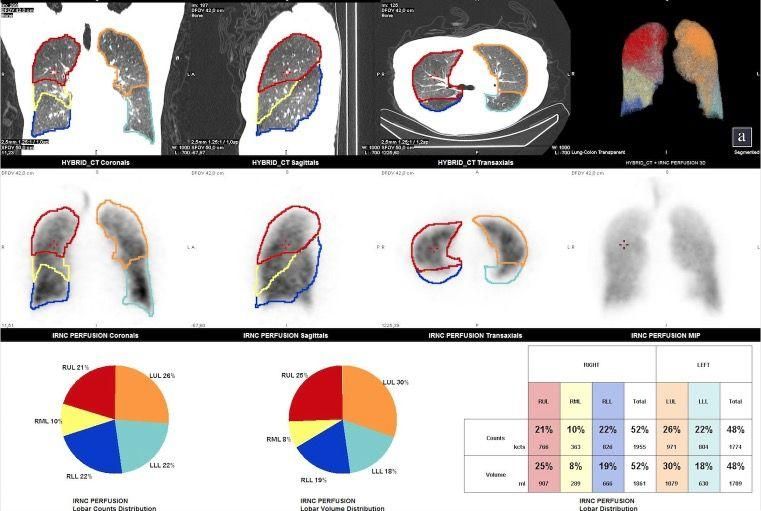

Zur Diagnose einer Lungenarterienembolie wird dieses Verfahren eingesetzt. Die Belüftung und die Durchblutung der Lunge werden unter Verwendung spezieller radioaktiv markierter Substanzen abgebildet, so dass Störungen erkannt werden können. Zudem kann eine Quantifizierung der Lungenfunktion vor Lungenoperationen, Tumorerkrankungen, chronisch obstruktiven Lungenerkrankungen oder Lungenemphysem zur Beurteilung der postoperativen Lungenfunktion durchgeführt werden.

Hierzu können mittels einer Fusion der Lungenszintigraphie mit einer CT-Aufnahme der Lunge mittels Software und einem geeigneten Auswerteverfahren, die Anteile einzelner Lungenlappen an der Gesamtfunktion der Lunge berechnet.